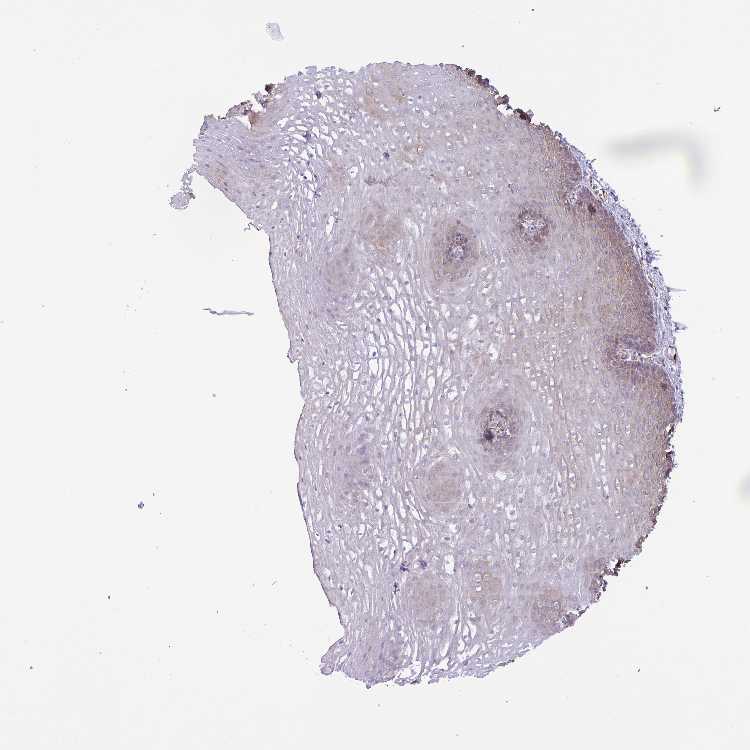

ESOPHAGUS - Antibody stainingi

Antibody staining in the annotated cell types in the current human tissue is reported as not detected, low, medium, or high, based on conventional immunohistochemistry profiling in selected tissues. This score is based on the combination of the staining intensity and fraction of stained cells.

Each image is clickable and will lead to virtual microscopy that enables deeper exploration of all samples and also displays staining intensity scores, fraction scores and subcellular localization as well as patient and tissue information for each sample.

Antibody HPA058931

Squamous epithelial cells Medium